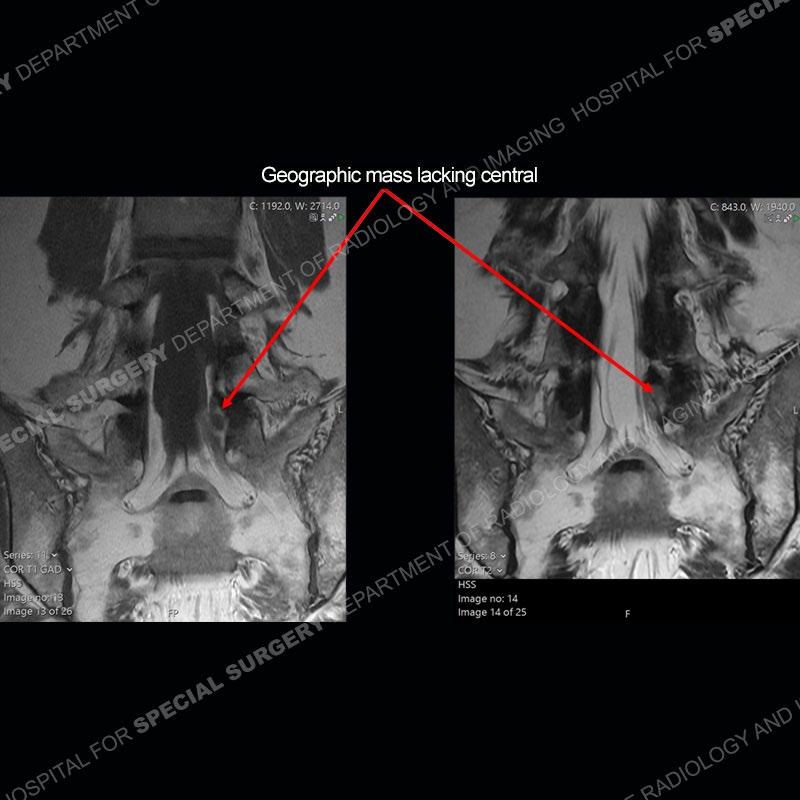

Post operative changes are seen on the left side at L5-S1 where there is near complete removal of the left sided L5 lamina, partial resection of the left L5-S1 facet joint, and resection of the left sided ligamentum flavum. In the anterolateral epidural space about the subarticular recess is a mass that demonstrates similar T1 and T2 signal characteristics to the adjacent degenerated disc. There is enhancement about the periphery of the mass, but the majority of this somewhat geographic or polyploid mass demonstrates no enhancement. The mass exerts prominent mass effect on the left S1 axillary sleeve/proximal nerve root. The left S1 nerve root shows enlargement and increased enhancement as compared to the contralateral right side.

Not as much of a diagnostic dilemma as some other cases but more so just a very nice example of what can be a difficult assessment at times. The evaluation of granulation tissue/scar/epidural fibrosis vs. disc herniation particularly in the earlier post operative period can be very difficult. Clues that can assist in identifying a disc herniation are a more geographic or polypoid nature to the mass, signal characteristics similar to the adjacent degenerated disc, mass effect upon the thecal sac/adjacent neural structures, and a typical enhancement pattern. As the disc material is avascular, as long as imaging is performed in a relatively rapid fashion after contrast administration (within 20-30 minutes), the granulation tissue around the disc will enhance but the disc material itself will not. If there is a marked delay between contrast administration and imaging, there may be diffusion of contrast into the disc making the assessment very difficult. The marked utility of contrast to help delineate disc vs. scar has led to our institution employing contrast fairly uniformly within the first two years following surgery.